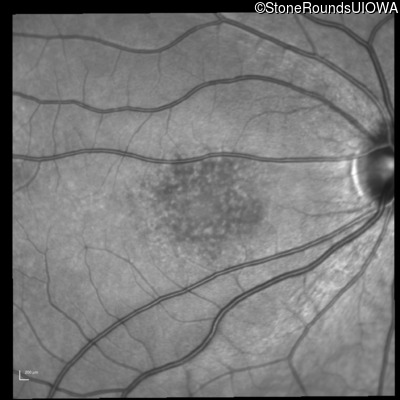

Infrared Fundus Photograph - Right - 20/160 -1 sc

Exemplar